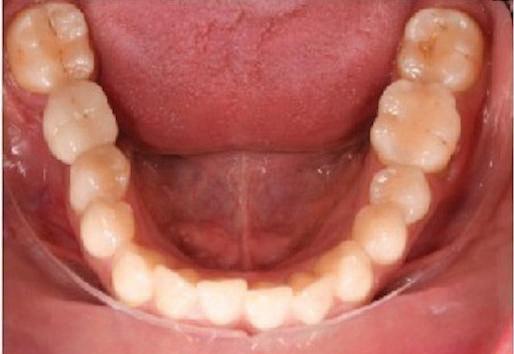

20 Dental Tribune Bulgarian Edition / октомври 2022 г. П ациентите със завършен растеж и скелетни проблеми обикновено представляват предизвикателство за ортодонт ската практика. Необходимостта от изваждане на зъби в комбинация с особеностите на възрастовата ортодонтия изисква особено внима ние. Фокусът върху критично важното значение на позицията на долните резци във връзка с дългосроч ната стабилност и постигането на оптимални оклузални взаимоотношения при затварянето на екстракционните пространства лесно може да излезе извън контрол. Когато към тези чисто кли нични проблеми се добави и стресът от натоваре ната практика, предизвикателството става още по-голямо. Всички тези фактори налагат използ ването на доказан подход с ясни и последовател ни стъпки, в което се разкрива силата на дисциплината „Алекзандър“ – предвидим протокол през целия процес на елиминиране на ротациите, ниве лиране на дъгите, затваряне на екстракционните пространства и финализиране на случая. Именно такъв е и случаят, който презентираме –екстракционен, скелетен клас 3 при възрастен па циент, лекуван по системата „Алекзандър“. ПРЕДВИДИМИ РЕЗУЛТАТИ ПРИ ПАЦИЕНТИ СЪС ЗАВЪРШЕН РАСТЕЖ И СКЕЛЕТЕН КЛАС 3, ИЗПОЛЗВАЙКИ ЕКСТРАКЦИОННО ЛЕЧЕНИЕ ПО ДИСЦИПЛИНАТА „АЛЕКЗАНДЪР“ Д-р Радой Димитров, България Преди започване на лечение клиничен случай | ортодонтия Фиг. 1а–1e Преди започване на лечение. Пациентът пристига в практиката с основното оплакване от невъзмож ност за нормално дъвчене. Снета е цялата необходима диагностична ин формация. Фиг. 1f–1h Снимки в профил и анфас. Фиг. 1i–1k Панорамна снимка, телерентгенография и анализ на телерент генография. Фиг. 1а Фиг. 1d Фиг. 1f Фиг. 1g Фиг. 1h Фиг. 1e Фиг. 1b Фиг. 1c Фиг. 1i Фиг. 1j Фиг. 1k

closed.

21Dental Tribune Bulgarian Edition / октомври 2022 г. ДИАГНОСТИЧНИ РЕЗУЛТАТИ: 1. Възраст на пациента: 21 години 2. Скелетен клас III (ANB 0) 3. Зъбен клас 3 4. Ръбцова захапка във фронта, кръстосана в дисталните участъци 5. Тясна горна челюст 6. Overjet – 0 мм, Overbite – 0 мм 7. Несъответствие на горната с долната средна линия 8. Единични контакти в ЦО 9. Хиподивергентен тип на растеж SN/MP – 33.5 10. Неравен гингивален контур 11. Неравна линия на усмивката 12. Тенденция за рецесии в долен фронт ПРЕПОРЪЧИТЕЛНО ЛЕЧЕНИЕ: Пълно ортодонтско лечение с метални брекети „Алекзандър“ Корекция на клас 3 захапката в областта на кучешките зъби с екстракция на първите пре молари в долна челюст Корекция на кръстосаната захапка в дистални участъци Коригиране на ръбцовата захапка във фронта Подобряване на ОJ и OB на пациента Стрипинг в долен фронт Подреждане на зъбите в горната и долната челюст Професионално хигиенизиране и профилактични дентални прегледи са препоръчителни на всеки 6 месеца. 1-ви месец След 1 месец са залепени брекети в горната челюст – поставена е еластична дъга. 016 NiTi. В долната челюст са елиминирани ротациите, поставена е стоманена дъга. 016SS, закалена с ток, и еластична верижка за затваряне на пространствата. 3-ти месец В долната челюст е поставена трета дъга – 17 x 25 NiTi с къси лигатури и верижка

В горната челюст се затварят пространствата с дъга .016SS и верижка. 5-и месец На 5-ия месец след залепяне на брекетите в долната челюст е поставена стоманена дъга 16 x 22 SS с четвъртито сечение, омега луп и тай бек. В горната челюст е поставена дъга 17 x 25 NiTi. Поради липсата на стабилни оклузални контакти са поставени лингвални верижки в областта на моларите, за да се предотврати нежелана ротация на 7-ите зъби. 6-и месец На 6-ия месец от началото на лечението са екстрахирани долните първи премолари, поставена е дъга 16 x 22 SS със затваряща чупка teardrop. Чупката се активира всеки месец по 1 мм с чинч-бек. клиничен случай | ортодонтия СТЪПКИ НА ЛЕЧЕНИЕТО Начало на лечението Лечението започва с поставяне на апарат за бърза експанзия в горната челюст. През първия месец от лечението са направени 24 оборота на апарата за експанзия. Залепени са брекети в долната челюст, поставена е дъга 17x25 CuNiTi, като са предпи сани клас 3 ластици (1/4”,4 1/2 oz) по време на сън, за да се осигури контрол върху торка на долните резци. Фиг. 2а Фиг. 3a Фиг. 4a Фиг. 3b Фиг. 4b Фиг. 3c Фиг. 4c Фиг. 3d Фиг. 4d Фиг. 3e Фиг. 4e Фиг. 5a Фиг. 5b Фиг. 5c Фиг. 5d Фиг. 5e Фиг. 6a Фиг. 6b Фиг. 6c Фиг. 6d Фиг. 6e Фиг. 7a Фиг. 7b Фиг. 7c Фиг. 7d Фиг. 7e Фиг. 2b Фиг. 2c Фиг. 2d

Dental Tribune Bulgarian Edition / октомври 2022 г.22 клиничен случай | ортодонтия 14-и месец В горната и долната челюст са поставени последни стоманени дъга с омега луп и тай бек – 17 x 25 SS с четвъртито сечение. Назначени е ластик за средната линия в комбинация с клас 3 ластик (1/4”, 6 1/2 oz). Контролни рентгенографии 13-и месец Екстракционните пространства са затворени. Направена е контролна панорамна снимка за оценка позицията на корените. Взето е решение за презалепване на брекетите на 12, 22 и пръстените на 36 и 46. 21-ви месец Средната линия в горната и долната челюст съвпадат. Ластиците са спрени. Свалени са пръстените и брекетите в горната и долната челюст, зигзаг ластици не са използвани поради благоприятните оклузални взаимоотношения. Фиг. 11j Ортопантомография в края на лечението. Фиг. 11k Телерентгенография след края на лечението. Фиг. 11l Анализ на телерентгенографията след лечението. Фиг. 11m Последователност на дъгите в горната и долната челюст Фиг. 11n Суперимпозиция на PreOp и PostOp ортопантомографии. 10-и месец Затварянето на пространствата е предвидимо и контролирано, без да се отварят пространства в зъбната дъга. Фиг. 8a Фиг. 8b Фиг. 8c Фиг. 8d Фиг. 8e Фиг. 10a Фиг. 10b Фиг. 10c Фиг. 10d Фиг. 10e Фиг. 9a Фиг. 9b Фиг. 9c Фиг. 9d Фиг. 9e Фиг. 9f Фиг. 11a Фиг. 11f Фиг. 11j Фиг. 11l Фиг. 11m Фиг. 11n Фиг. 11k Фиг. 11g Фиг. 11h Фиг. 11i Фиг. 11b Фиг. 11c Фиг. 11d Фиг. 11e

Dental Tribune Bulgarian Edition / октомври 2022 г. 23клиничен случай | ортодонтия реклама Лечението е продължило 21 месеца. Проведено е домашно избелване с индивидуални шини. За автора: Д-р Радой Димитров завършва с отличие Факултета по дентална медицина към МУ–София през 2015 г. В продължение на 5 години работи в няколко водещи практики в София, като през 2019 г. заедно със своята съпру га д-р Траяна Димитрова основават собствена практика в гр. Гоце Делчев –Dimitrovi Dental Care. Посещава редица курсове за повишаване на квалификаци ята, но най-сериозен тласък в развитието на ортодонтската си практика получава след завършването на комплексната ортодонтска програма, воде на от д-р Иван Горялов, базирана на дисциплината „Алекзандър“ – система с повече от 50 години опит в целия свят. Д-р Димитров е член на Българския изследователски клуб „Алекзандър“. Взе ма участие като гост-лектор в симпозиума с международно участие The Power of the Alexander Discipline, който се проведе на 14–15.05.2022 г. С д-р Ди митров можете да свържете на тел. +359885 252 025. Заключение Представеният случай е ярък пример за възможностите и красо тата на дисциплината „Алекзандър“ – приложен е утвърден под ход с ясни правила и са постигнати очакваните цели. Резулта тът ще бъде дългосрочно стабилен, тъй като са спазени всички правила, които се отнасят към максимално комфортната пози ция на зъбите в края на лечението. Постигнати са красива усмив ка и стабилна оклузия. ПОСТИГНАТИ РЕЗУЛТАТИ ОТ ЛЕЧЕНИЕТО 1. Коригирана ръбцова захапка 2. Коригирана клас 3 захапка в областта на ку чешките зъби 3. Коригирана кръстосана захапка в дисталните участъци 4. Коригиран овърджет и овърбайт 5. Разширена е горната зъбна дъга 6. Подредени зъби в горната и долната челюст 7. Постигната е стабилна захапка с множество контакти в ЦО 8. Драматично е подобрена дъвкателната функ ция 9. Подобрена е линията на усмивката ДРУГИ ПРОВЕДЕНИ ДЕНТАЛНИ ПРОЦЕДУРИ 1. Домашно избелване на зъбите 2. Екстракция на мъдреците Фиг. 12a Фиг. 12b Фиг. 12c Фиг. 12eФиг. 12d Фиг. 12f Фиг. 12g Информация за дати, цени и отстъпки www.bracescourses.com 0889 22 55 01 Практически курсове лектор д-р Иван Горялов Дисциплината „Алекзандър“ ПЪТЯТ КЪМ СУПЕРУСМИВКИТЕ 100% връщане на цялата сума, ако не сте удовлетворени след преминаване на Ниво 1 Директно и индиректно залепяне на брекети Анализ, диагноза и план на лечение Лечение на клас 2 дълбока захапка Екстракционно лечение Лечение на клас 3 отворена захапка НИВО 5НИВО 1 НИВО 2 НИВО 3 НИВО 4